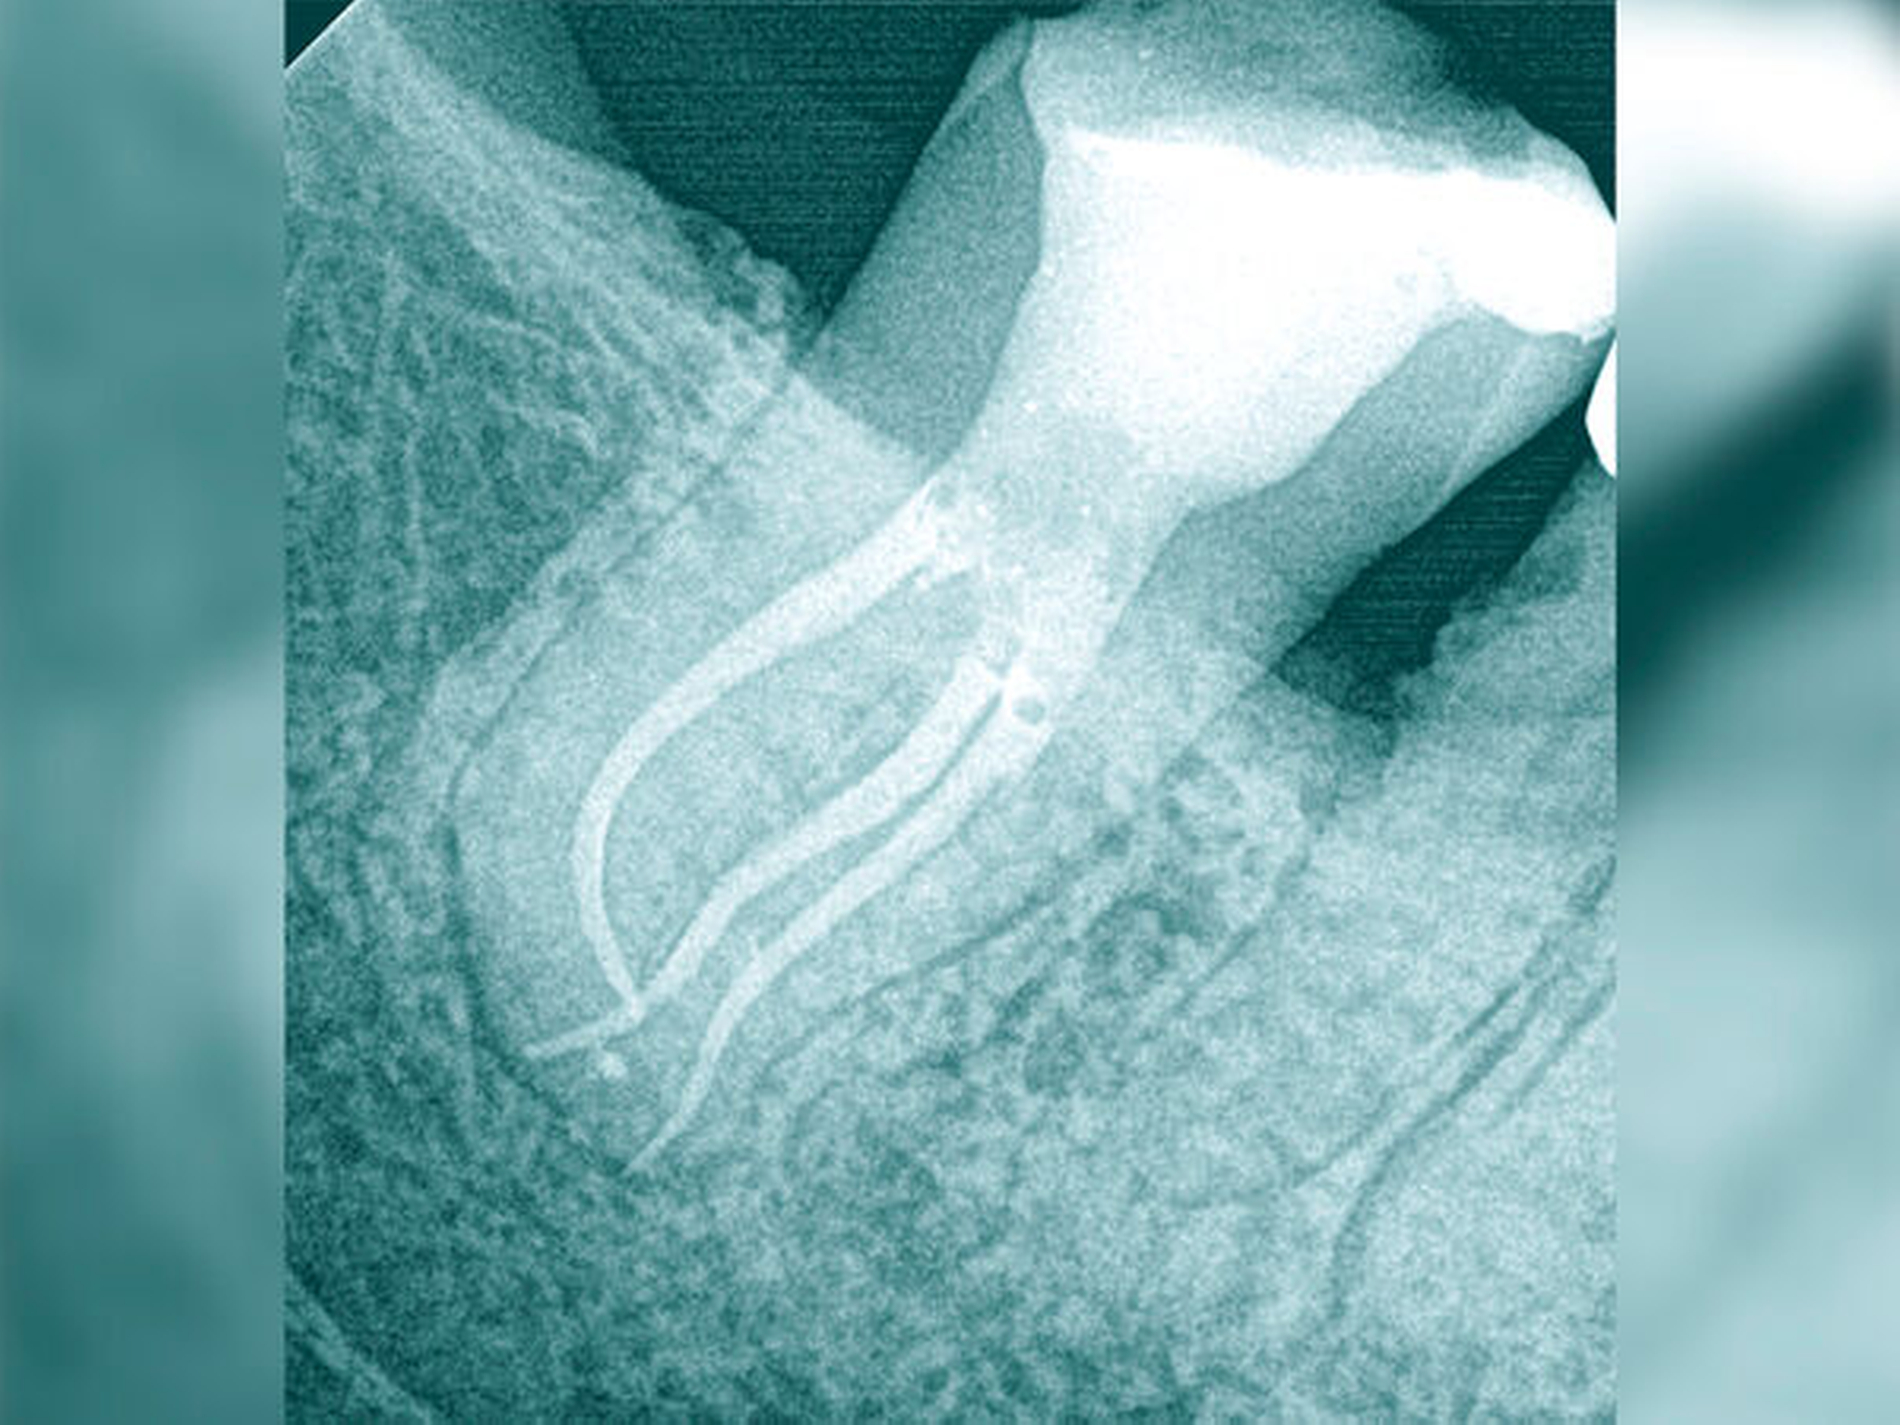

Der Schwierigkeitsgrad entspricht dem Grad II. Sowohl in der Diagnostik als auch in der Therapie liegen erhöhte Anforderungen vor. Der Allgemeinzustand, die verringerte Compliance, die eingeschränkte Mundöffnung und das erschwerte intraorale Röntgen ließen bereits im Verlauf der Befundaufnahme eine größere Schwierigkeit erkennen. Die Wurzelspitze ist stark nach mesial gekrümmt. Der sehr kleine Krümmungsradius kann eine Instrumentenfraktur begünstigen. Die Bedingungen für einen aseptischen Zugang unter Kofferdam lagen nicht vor, so dass vorbereitend eine Kariesentfernung und eine dentinadhäsive präendodontische Restauration erforderlich wurden (Abbildungen 13a und 13b).

Im Verlauf der IKD bestätigte sich eine partielle Pulpanekrose mit teilweise noch durchblutetem Pulpagewebe. Die Wurzelkanalbehandlung erfolgte mehrzeitig unter Verwendung von rotierenden NiTi-Instrumenten, der Wurzelkanal konnte so vollständig verschlossen werden (Abbildung 13c). Die Prognose aus endodontischer Sicht ist gut. Eine postendodontische Versorgung mit chirurgischer Kronenverlängerung ist zur langfristigen Sicherung des Erfolgs erforderlich.